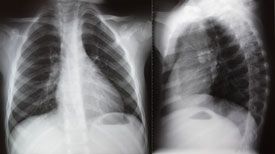

Researchers have reported that acute myocardial infarction (MI) patients who are exposed to low-dose ionizing radiation from imaging and therapeutic procedures may be at increased risk of cancer.

The Canadian study found that 77% of patients had undergone at least 1 cardiac imaging or therapeutic procedure involving low-dose ionizing radiation in the first year after their MI. Overall, 12,020 cancers were detected during follow-up. While there was a broad distribution of cancers, those affecting the abdomen/ pelvis and thorax accounted for roughly two-thirds of cancers.

The analysis showed a dose-dependent relation between radiation exposure from cardiac procedures and subsequent cancer risk. Thus, for every 10 millisieverts (mSv) of radiation, there was a 3% increase in the risk of age- and sex-adjusted cancer during a mean 5-year followup. In addition, while the majority of patients were exposed to low or moderate radiation levels, a “substantial” group was exposed to high levels. These patients were usually young males with fewer comorbidities. The level of exposure to lowdose ionizing radiation was higher when patients were treated by a cardiologist than a general practitioner.